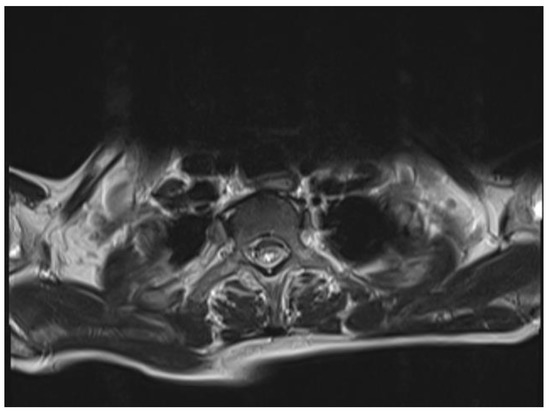

The chest and brain tomography did not display any abnormalities. The spinal MRI performed on the second day of hospital admission showed irregular intramedullary signal enhancement on the T2 sequence with diffuse lesions ranging from the sixth cervical vertebra to the seventh dorsal vertebral (Figure 1). The T1 sequence showed the spinal cord with multiple hypointense lesions centrally located at the cervical–dorsal level (Figure 2), while the transversal image T2-weighted image of the spinal cord showed hyperintense lesions in the white matter and in the posterior portion of the spinal cord (Figure 3).

Figure 3.

T2-weighted image of the spinal cord: hyperintense lesions in the white matter and in the posterior portion of the spinal cord.

MRI has an important role in the diagnosis and classification of TM, as it allows us to identify hyperintense spinal cord injury in T2-weighted images, and when it affects at least three vertebral segments in the sagittal slices, TM is classified as LETM [3]. T2- weighted MRI demonstrated an intramedullary increased signal in the central portion of the spinal cord as the most common finding [5]. MRI images in immunocompetent patients with TM show that the cervicothoracic cord is affected more frequently, as in our case, unlike immunosuppressed patients, in which tropism has been seen in the cauda equina or the conus medullaris [13]. The aforementioned findings coincide with the RMI in the case report presented, in which hyperintense cervicothoracic spinal cord involvement was observed in the T2-weighted image. This was specifically seen in patients with NMO (anti-AQP4 Ab) associated with patients with SLE and Sjögren’s disease [3,14]; while there is evidence of markedly hyperintense foci on T2 described as “Bright Spotty Lesions”, characteristic for NMO, in this case, anti-AQP4 antibody sera were not performed. However, the results of the IgM serological test for cytomegalovirus was positive, which confirmed the acute installation of the infectious image.